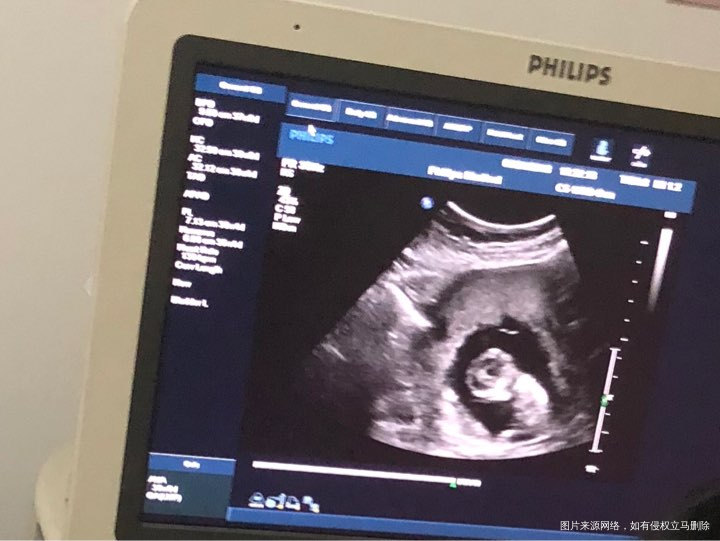

今天12周NT,顺利通过,第一次看到我的大头宝宝,已经长到52毫米了,第一次听到胎心,像小火车一样呼啦呼啦,这种感觉好神奇,生殖中心顺利毕业,以后转产科了